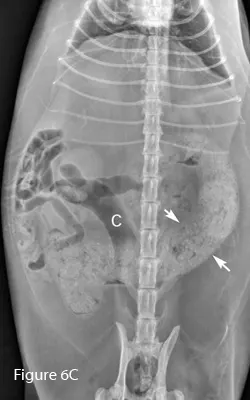

A backup of ingesta proximal to the obstruction site can cause bowel distention (See Figures 2–6, below). Complete and some chronic partial obstructions can cause significant bowel dilation, and often the colon is empty. Depending on the obstruction site, the segment of bowel distention may be short or long. Compared with the small intestine, the colon is typically larger in diameter and contains fecal material. Differentiating small intestine from colon is crucial for accurate diagnosis: mistaking colon for small intestine can lead to incorrect diagnosis of small bowel obstruction, while mistaking distended small intestine for colon can lead to a missed diagnosis of small intestinal obstruction (Figure 6, below). Both lateral and ventrodorsal views are essential for accurate assessment, although both may not be presented in this collection.

Lateral (Figure 6B) and ventrodorsal (Figure 6C) abdominal radiographs of severely distended segment of bowel identified sonographically and properly diagnosed as severe small intestinal obstruction (arrows). Of note, there is fecal-like material in the small intestine. An ileocecocolic mass was diagnosed during exploratory laparotomy. This mass was apparently obscured by gas during ultrasound examination. (C = colon)